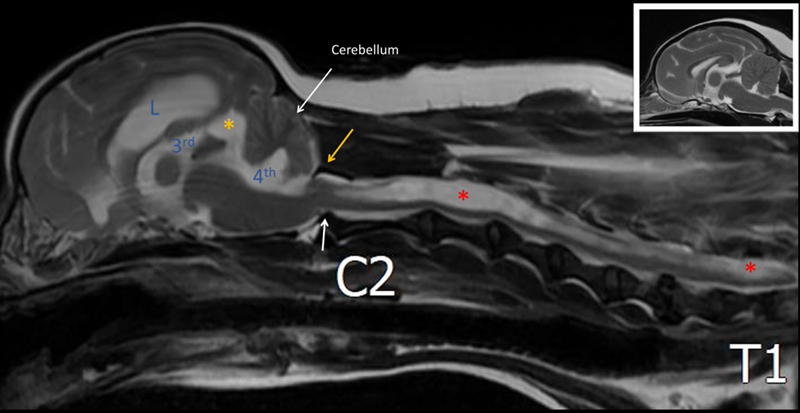

뇌 영상에서 노란색 화살표로 표시된 부위는 COMS 소견으로 확인되었습니다. COMS는 후두골 이형성 증후군의 약자로, 선천적으로 뒤통수 뼈의 형성이 충분히 발달하지 않는 질환입니다. 이로 인해 뒤통수에 위치한 소뇌가 압박을 받아 아래쪽으로 탈출하는 소견이 관찰되며(흰색 화살표) ▼

이러한 변화는 CSF 순환 장애를 유발합니다. 그 결과 빨간색 별표로 표시된 것처럼 척수 중심관의 확장이 확인되었고, 뇌에서도 뇌수두증이 동반되어 있었습니다.

척수 중심관의 확장은 경추부터 요추(C2~L3 level)까지 광범위하게 분포하고 있었으며, 특히 C2-3와 L2-3 부위에서 가장 심하게 관찰되었습니다.

두경부 정중 시상 단면상 후두부 이형성과 관련하여 소뇌 형태 이상이 확인되며, 외측 뇌실, 제3뇌실 및 제4뇌실의 확장이 관찰됩니다. 또한 medullary kinking 및 dorsal angulation of axial dens가 동반되어 있습니다.

제3뇌실과 인접한 quadrigeminal cistern 부위에 small cystic lesion이 관찰되며, quadrigeminal cyst가 의심됩니다.

경추부터 요추(C2~L3 level)까지 광범위한 척수 중심관 확장이 확인되었으며, 시상 단면상 중심관 확장이 가장 심한 부위는 C2-3 및 L2-3로 평가됩니다.